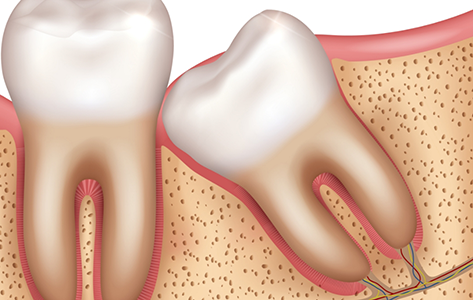

Illustration of wisdom tooth pressing up against another tooth

There is a good chance that one of our three oral surgeons will recommend wisdom teeth removal if:

• They are difficult to clean because of their orientation, increasing the risk of potential cavities

• They are impacted and pressing against nearby teeth, causing them to move

• They are pressing against a nerve that is causing pain or numbness in areas of your mouth

• They are unable to fully erupt because they are impacted